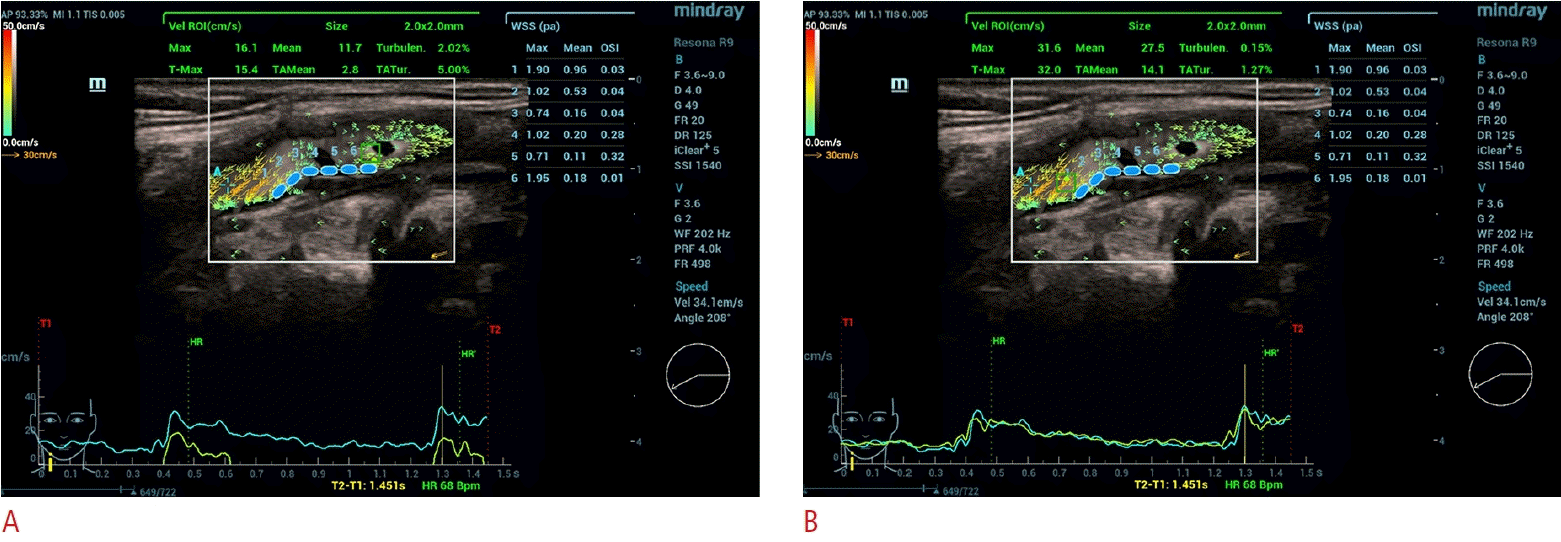

Fig. 2.

Vector flow imaging (VFI) measurements of the upstream and downstream carotid plaque surfaces.